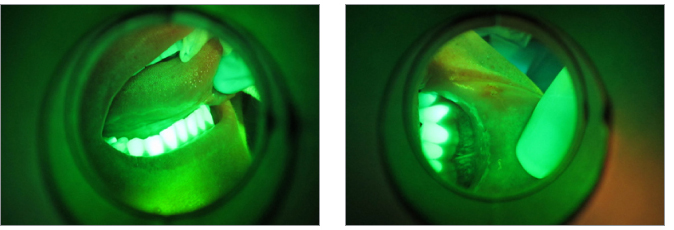

10) Il Velscope è un ausilio diagnostico che sfrutta la fluorescenza e mette in evidenza variazioni della vascolarizzazione di tessuti molli